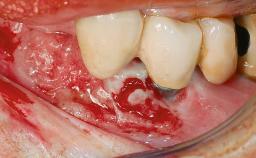

In 2004, the patient, a smoker, began dental treatment at the ACTA graduate clinic. She was a TV producer exposed to a lot of stress in her job and had a sick husband. Her maxillary teeth had been extracted, as had the mandibular canines, premolars, and molars, with the exception of tooth 34. She received a complete maxillary denture and a mandibular skeleton denture. In October 2007, her maxilla was augmented by an oral and maxillofacial surgeon; in March 2008, implants (Biomet 3i, Palm Beach, Florida, USA) were inserted at that same clinic. In 2008, the patient was presented at the Department of Oral Implantology and Prosthetic Dentistry to request restorations for her implants. An implant-supported overdenture was planned. She also asked if we could restore her occlusion with fixed prosthetics.